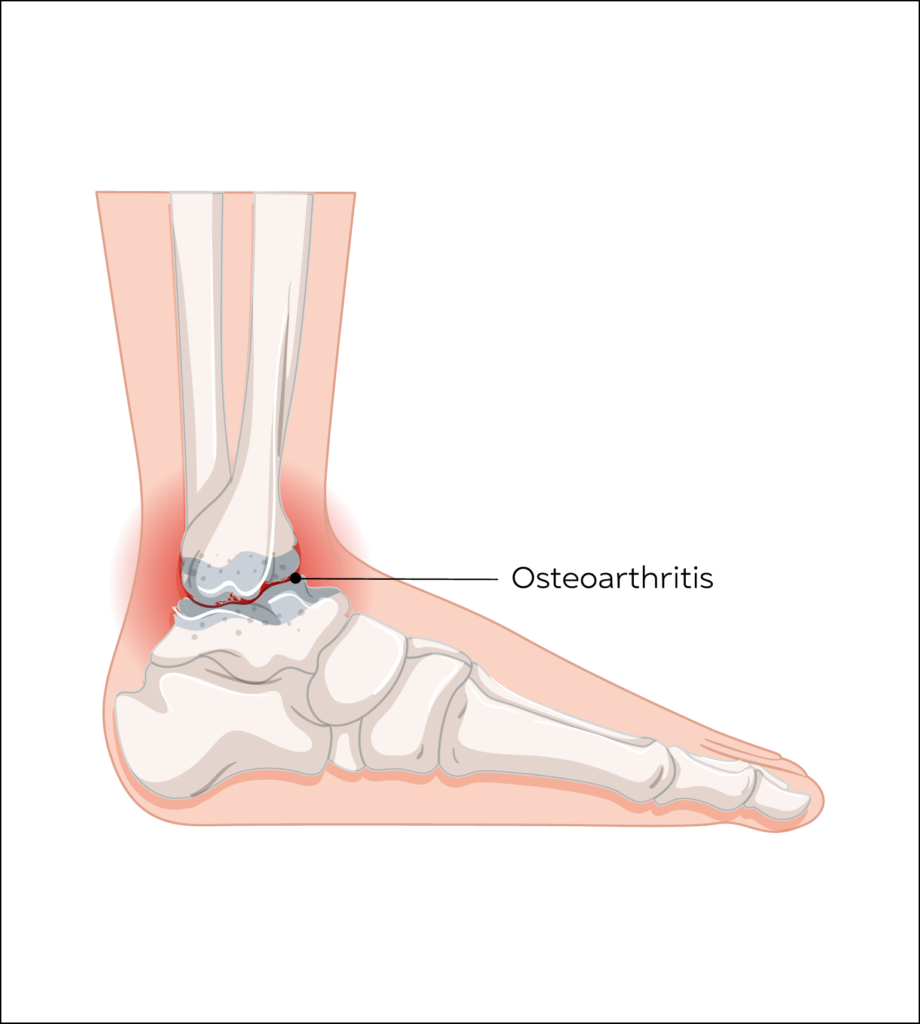

Arthritis of Ankle, Mid Foot & Big Toe

Osteoarthritis is a painful degenerative condition affecting any joint with articular cartilage due to gradual wear and tear of the articular cartilage, which protects the bone ends.

It is not as common as hip or knee osteoarthritis but is increasing in incidence.

Pain, swelling and restriction of joint movements and later physical deformity of the foot and toes can occur.

Osteoarthritis cannot be cured by medication, but injections administered into the joint using steroids or Hyaluronic acid do give short and long term relief of symptoms.